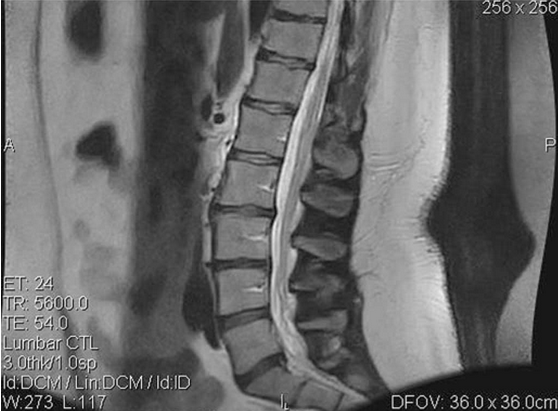

A 35-year-old female presented at an outpatient clinic in July 2006 complaining of LBP. The back pain was associated with numbness and recurrent right leg pain. The treating physician noted that the patient’s condition had been chronic since December 2004. These symptoms affected her ability to lift clients – a required part of her occupational duties – and were aggravated by sitting and prolonged standing. The patient weighed 291lb and was 5’ 8” tall. Her history was significant, with two motor vehicle accidents (in 1994 and 2002). Magnetic resonance imaging (MRI) of the lumbar spine performed on 19 July 2006 revealed a mild to moderate disc protrusion at L5/S1, eccentric to the right, impinging on the right S1 nerve root (see Figure 1). Mild degenerative changes with minimal bulging were also noted at L2/L3 and L3/L4. Upon initial examination, the patient presented limited lumbar range of motion (ROM), with pain in all planes, positive nerve root tension tests and decreased sensory and motor function of the right lower extremity.

At initial treatment, the patient reported pain at 7 on a 0–10 scale; at the end of the treatment protocol she reported pain at 1. A reduction in the duration of pain was noted as well: pain initially occurred 75% of the time, but decreased to 10% of the time at completion of treatment. At final evaluation, the examiner noted an improvement in lumbar ROM tests: flexion increased from 42 to 58º, extension increased from 12 to 26º, left lateral flexion increased from 14 to 25º and right lateral flexion increased from 12 to 24º. Orthopaedic and neurological findings were noted as normal. Limited follow-up MRI of the lumbar spine performed on 22 September 2006 revealed a decrease in the excursion of the disc at L5/S1 on T2-weighted sagittal images (see Figure 2).

Figure 1: Pre-treatment Magnetic Resonance Image

Figure 2: Pre-treatment Magnetic Resonance Image